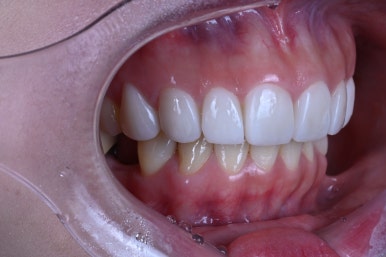

어디에서 보아도 원래 치아의 어두웠던 색상은 보이지 않고,

치아가 너~무 말 이빨처럼 커보이지도 않고, 자연스러운 생김새를 갖고 있습니다.

아래 치아와 비교해보시면 더욱 더 뚜렷한 색상차이를 확인하실 수 있죠.

입안에 위치하고, 눈코입과 함께 보면 요 색상이 꽤나 자연스러움을 아실 수 있으실겁니다.